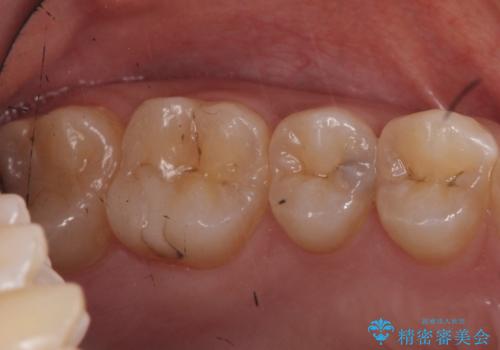

- 健診にて来院。

症状はないものの奥歯に黒ずんだ箇所があるため治療を進めていくことになりました。

笑うと外から見える場所であるため白い詰め物での治療となりました。

外からも確認できる虫歯だけでなく、歯の奥の面の虫歯も残さず除去しました。

残った歯の量が多かったためインレータイプでの修復となりました。